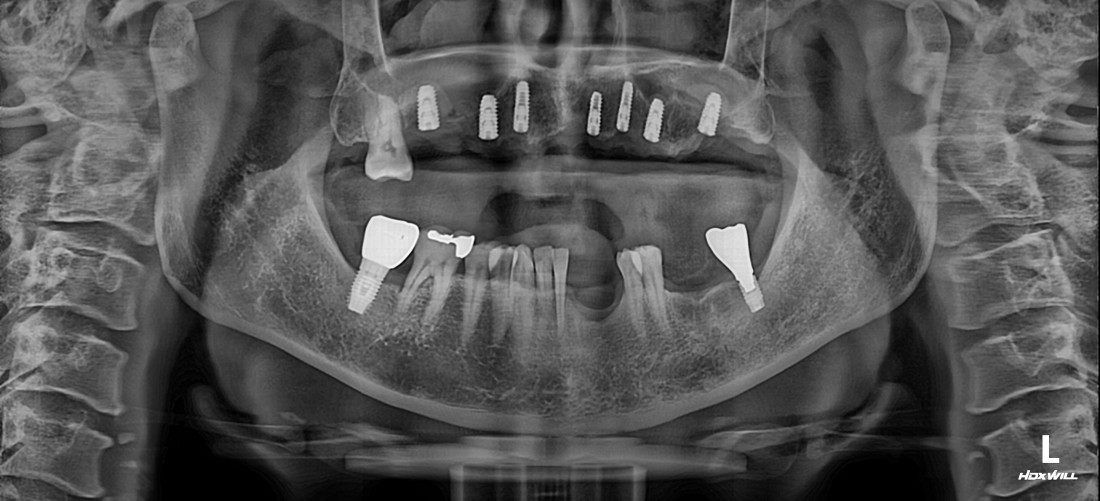

전남광주 임플란트 치과에서는

디지털가이드 임플란트 수술방법으로

한 번에 8개 이상의 임플란트를

심을 수 있습니다.

위, 아래 전체 임플란트를

단 두 번의 수술만으로 완성할 수 있어

임플란트 치과에 자주 내원하지 않으셔도 되고,

붓기 / 출혈 / 통증도 적기 때문에

빠른 회복을 기대할 수 있습니다.